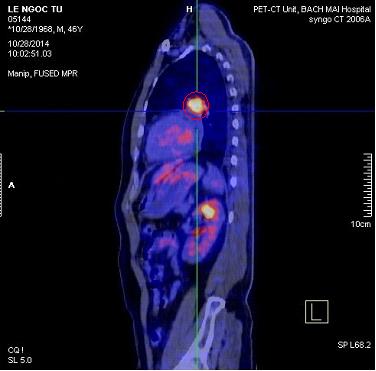

- Bệnh nhân được chụp PET/CT đánh giá sau 6 đợt hóa chất

Hình 6. Hình PET/CT sau 6 đợt hóa chất: còn tổn thương tăng FDG ở thùy trên phổi T (kích thước 25x15mm), max SUV: 6,0

(vòng tròn đỏ)